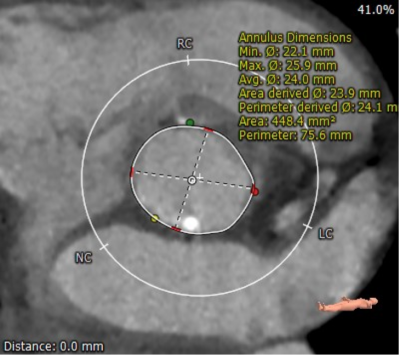

患者男性,70岁,重度钙化型主动脉瓣狭窄,STS评分8.6%,常规外科手术高风险。术前心脏超声提示主动脉瓣严重增厚钙化,峰值流速5.4m/s,平均跨瓣压差82mmHg。CT评估结果显示主动脉瓣重度钙化,瓣环平均直径23.9mm,瓣环面积448.4mm²。左冠脉开口高度8.5mm,右冠脉开口高度12.2mm。该患者左、右冠状动脉开口高度低,左冠瓣叶较长伴钙化,且瓦氏窦较小,窦管交界处高度低,冠状动脉阻塞风险高,手术操作复杂。

主动脉瓣瓣环